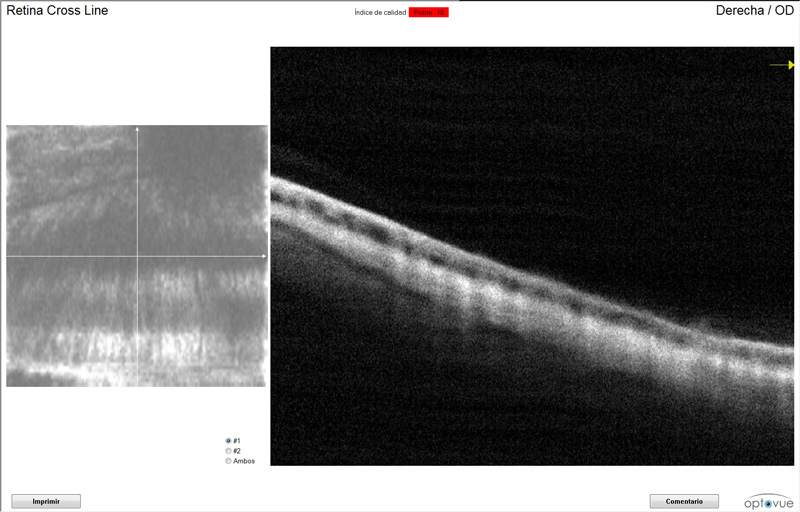

- OCT fondo ocular

Se le practicó también una OCT del fondo ocular que determinó que padecía una degeneración de retina y excavación del nervio óptico en el ojo afectado por glaucoma.

El aumento de la presión intraocular lo primero que provoca son lesiones en el nervio óptico, pero en algunos casos como en el de Riky también está gravemente afectada la retina.